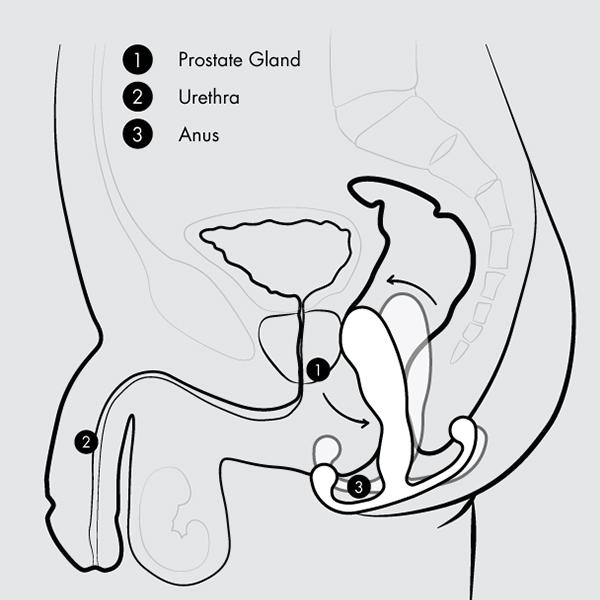

Dankzij de revolutionaire Multi-Axial Motion Architecture (MAMA) beweegt de Eupho Trident vrij in meerdere richtingen: zijwaarts, op en neer én roterend. Elke contractie van je bekkenbodemspieren zet de stimulator in beweging, waardoor een golf van sensaties ontstaat die je prostaat en anale kanaal verfijnd masseren.

Tijdens geslachtsgemeenschap komt de Eupho Trident pas écht tot leven: de slanke body beweegt vrij mee met de stoten van je partner, waardoor je orgasmes dieper, krachtiger en langer worden. De gebogen kop raakt je prostaat direct, terwijl de perineum-tab en de Kundalini-tab externe stimulatie toevoegen – samen goed voor een orkest van prikkels dat je hele lichaam laat meetrillen.